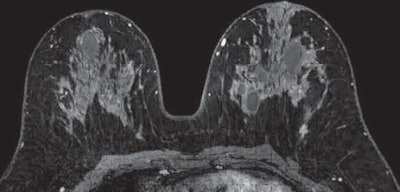

Lehman and colleagues specifically chose MR images obtained through a variety of acquisition techniques at various institutions to gain a "representative real-world set of images on which to test the utility of the CAD system," they wrote.

The selection and order of MR images were randomized for each reader to further minimize the potential for bias. Color overlays and CAD tools were available and used at the discretion of the radiologist, while non-CAD interpretations included visual assessment.